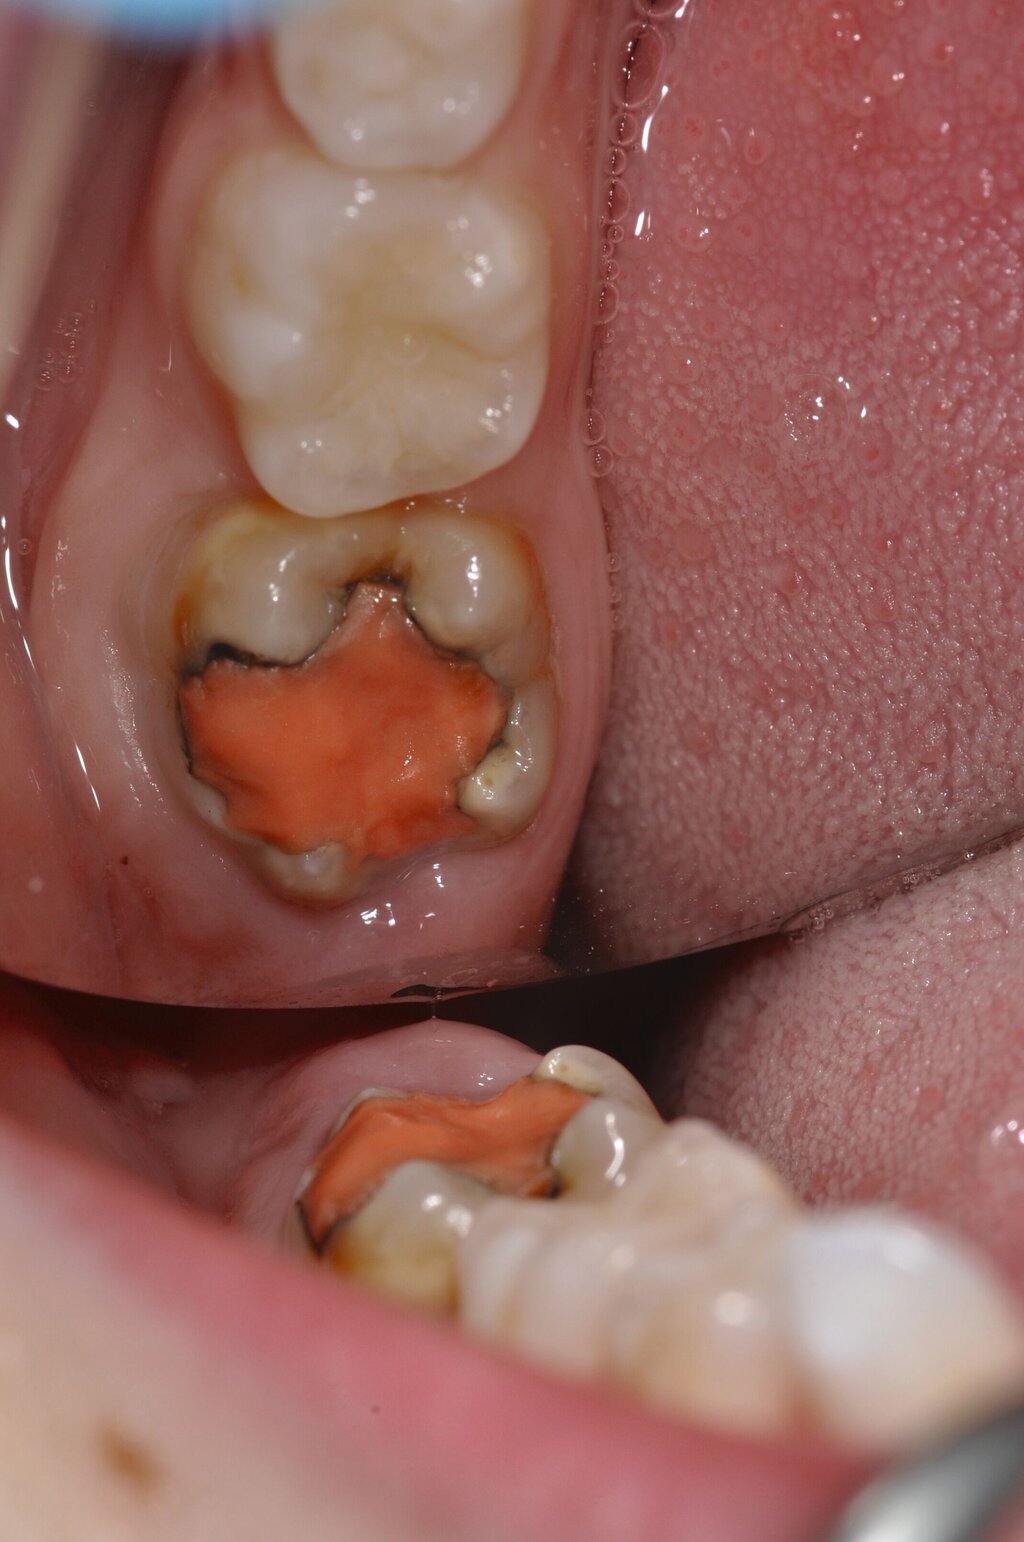

Diese Klassifikation dient als Grundlage für die Therapieempfehlungen. Deutlich wird, dass aufgrund der Symptomatik die Therapie der Zähne höchst unterschiedlich ausfällt. Dass etwa eine Opazität ohne Überempfindlichkeit (Index 1, Abbildung 1) ein anderes therapeutisches Vorgehen erfordert als ein Zahn mit nahezu komplettem Einbruch der Zahnoberfläche und mit Hypersensitivität (Index 4, Abbildung 2), ist offensichtlich.

Die Therapie C hat das Ziel, MIH-Zähne vorübergehend zu versorgen, bis der vollständige Durchbruch der Zähne eine adhäsive Restauration ermöglicht, um die hypersensiblen Zähne zu desensibilisieren oder/und die Mitarbeit für die weitere Behandlung aufzubauen. Vor dem Hintergrund des erhöhten Kariesrisikos dieser Zähne (Abbildung 2) muss durch die Maßnahmen eine Kariesprogression vermieden werden.

Der Vorteil der Methode ist, dass die betroffenen Zähne auch ohne Lokalanästhesie und Präparation versorgt werden können. Die temporäre Versorgung ermöglicht es, die Patienten an die zahnärztliche Behandlung zu gewöhnen. Häufig führt diese temporäre Versorgung auch zu einer Reduktion der Hypersensitivität der MIH-Zähne. Nachteil der GIZ-Versorgung ist das Risiko einer Füllungsfraktur oder eines vollständigen Verlusts der Füllung (Abbildung 4). Aktuelle Erhebungen bestätigen eine Erfolgsrate von über 80 Prozent nach einem bis zwei Jahren [Durmus et al., 2021; Mahfouz et al., 2025].

Der Behandlungsfall (Abbildung 4d) veranschaulicht die Schwächen des Verfahrens. Wird das Angebot der regelmäßigen Kontrollen nicht wahrgenommen, so droht bei Verlust der Füllung die Kariesprogression. In dem vorliegenden Fall konnte jedoch eine endodontische Maßnahme vermieden und durch die selektive Kariesentfernung die Zahnhartsubstanz weitestgehend erhalten werden.